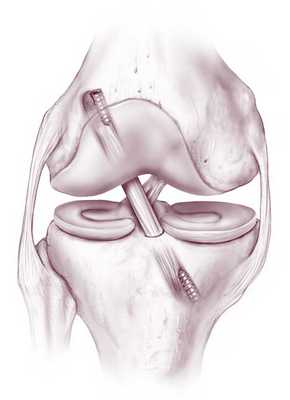

Хирургическое лечение разрыва передней крестообразной связки заключается в артроскопической реконструкции передней крестообразной связки. Артроскопия - метод эндоскопического выполнения операции на суставах. Операции выполняются при помощи очень тонких инструментов и специальной оптики, соединенной с цифровой видеокамерой (рис.2). Во время операции хирург смотрит на монитор и видит все, что происходит в данный момент в суставе, с большим увеличением - от 40 до 60 раз. Использование современных инструментов и высокочувствительной оптики позволяет выполнять тончайшие манипуляции на коленном суставе с минимальным повреждением окружающих структур и самого сустава (например, сшивание или удаление части менисков, пересадка хряща, реконструкция связок) - и все это через 2-3 небольших разреза. После подобной операции пациент обычно выписывается на этот же день.

Для реконструкции передней крестообразной связки в настоящее время в ведущих клиниках спортивной медицины используются трансплантаты, представляющие собой отрезки тканей человека. В мировой практике используется несколько источников трансплантата: аутотрансплантат из связки надколенника, аутотрансплантат из подколенных сухожилий, аллотрансплантаты.

- Реконструкция из связки надколенника. Данная связка соединяет надколенник с большеберцовой костью. Аутотрансплантат отсекают от большеберцовой кости и надколенника с костными фрагментами С помощью костного фрагмента в дальнейшем осуществляется фиксация аутотрансплантата в костном канале. Этот прием не только повышает прочность крепления трансплантата к новому ложу, но и обеспечивает более быстрое его сращение с последним, так как на сращение губчатой кости в канале, стенки которого представлены губчатой структурой, требуется 2—3 нед, что значительно меньше срока сращения такой связки или сухожилия с костью.Края разрезанной связки зашиваются. В большеберцовой и бедренной костях просверливаются каналы, выходящие в полость коленного сустава. Внутренние отверстия этих каналов в суставе находятся в том же самом месте, где находились места прикрепления передней крестообразной связки к суставным поверхностям бедренной и большеберцовой костей. Трансплантат связки проводится в полость сустава через костный канал большеберцовой кости. Концы протеза фиксируются в костных каналах при помощи специальных металлических или биополимерных рассасывающихся шурупов. Именно этот метод чаще всего используется в большинстве клиник мира.

Любая пластическая процедура на ПКС в настоящий момент выполняется методом малоинвазивной артроскопии. Артроскопический сеанс проходит закрытым способом под спинномозговой анестезией. Операция относится к щадящему типу хирургии высокой точности, поэтому мягким тканям, нервным и сосудистым образованиям не причиняется ущерб. Кроме того, манипуляции проводятся сугубо на пострадавшем участке, а после вмешательства никаких рубцов и шрамов не остается.

Чтобы осуществить реконструкцию поврежденного элемента, достаточно сделать один 5-мм прокол для оптического зонда, в который встроена миниатюрная видеокамера, и 1-2 дополнительных доступа (не более 8 мм в диаметре). Через вспомогательные отверстия хирург микрохирургическими инструментами будет заниматься воссозданием испорченной области. Зрительный контроль обеспечивает артроскоп (эндоскопический зонд), который выводит изображение оперируемой зоны на монитор в 40-60-кратном увеличении. Оперативное вмешательство может быть выполнено несколькими способами, рассмотрим их дальше.

В данном случае пересаживается фрагмент сухожилий пациента, взятый из мышц бедра, иногда берут материал из связок или сухожилий надколенника. На функциональности донорского участка это никак не отражается. Техника выполнения реконструкции заключается в удалении разорванных связочных структур с последующим внедрением на их место подготовленного трансплантата из сухожилий.

Зона «забора» материала.

Концевые участки сухожильного лоскута вдеваются в просверленные каналы бедренной и большеберцовой кости и натягиваются до нужных параметров, после чего закрепляются биоразлагаемыми винтами либо садятся на специальные петли. Через несколько месяцев без проблем происходит их полное врастание в кость. Методика хорошо изучена и имеет внушительную доказательную базу эффективности, поэтому является на сегодняшний день самой применяемой тактикой лечения ПКС, «золотым стандартом» ортопедии и травматологии.